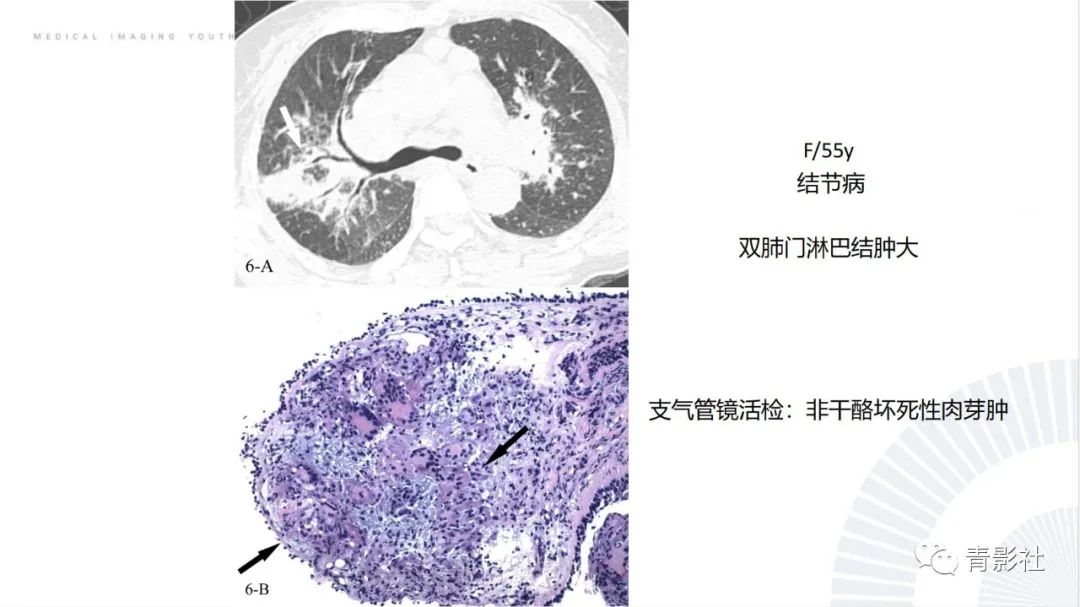

【PPT】肺部反晕征影像诊断思维-5